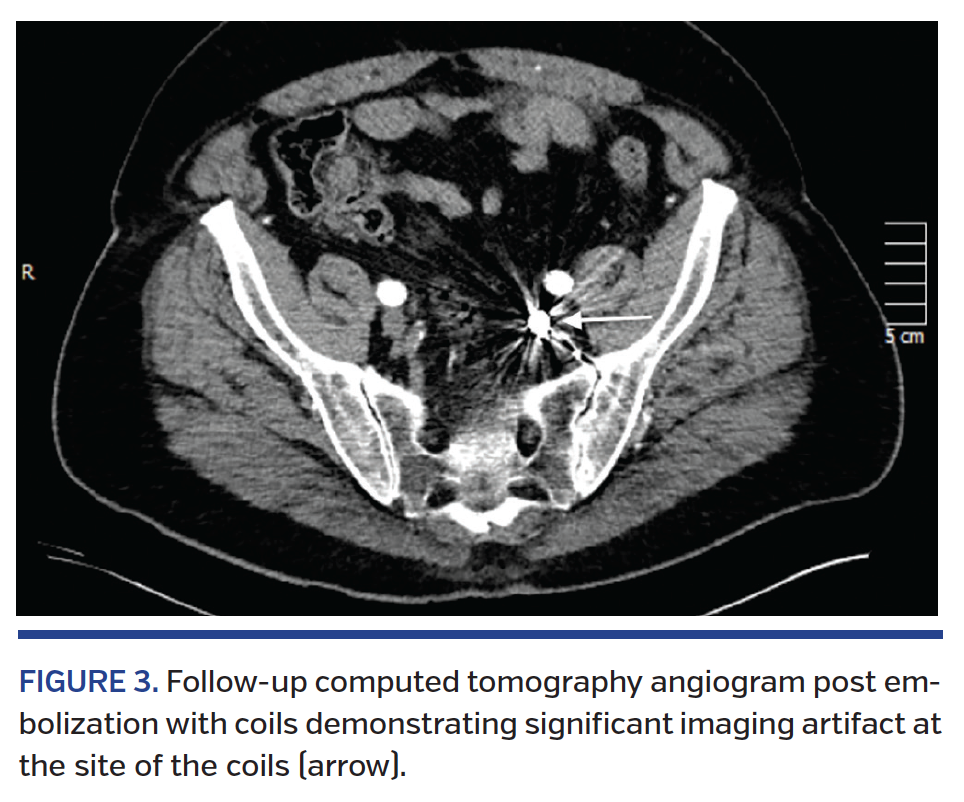

Fluoroscopy of the mechanical aortic valve in orthogonal views confirmed severely restricted valve leaflets. Coronary angiogram revealed normal, right-dominant coronary

anatomy with a thrombotic subtotal occlusion of the left anterior descending (LAD) artery and first diagonal branch bifurcation with Thrombolysis in Myocardial Infarction (TIMI) 2 flow into both territories (Figure 2). Thrombectomy of the LAD was performed using an Export catheter (Medtronic, Minneapolis, Minnesota) with 3 passes followed by thrombectomy of the diagonal branch with 5 passes, retrieving large pieces of thrombi (Figure 3). Final angiograms revealed a small residual thrombus in the mid-segment of the diagonal branch with TIMI 3 flow to both LAD and

diagonal territories (Figure 2). Right heart catheterization revealed elevated pressures with a pulmonary artery pressure of 70/25 mmHg and a mean pulmonary capillary wedge pressure of 30 mmHg.